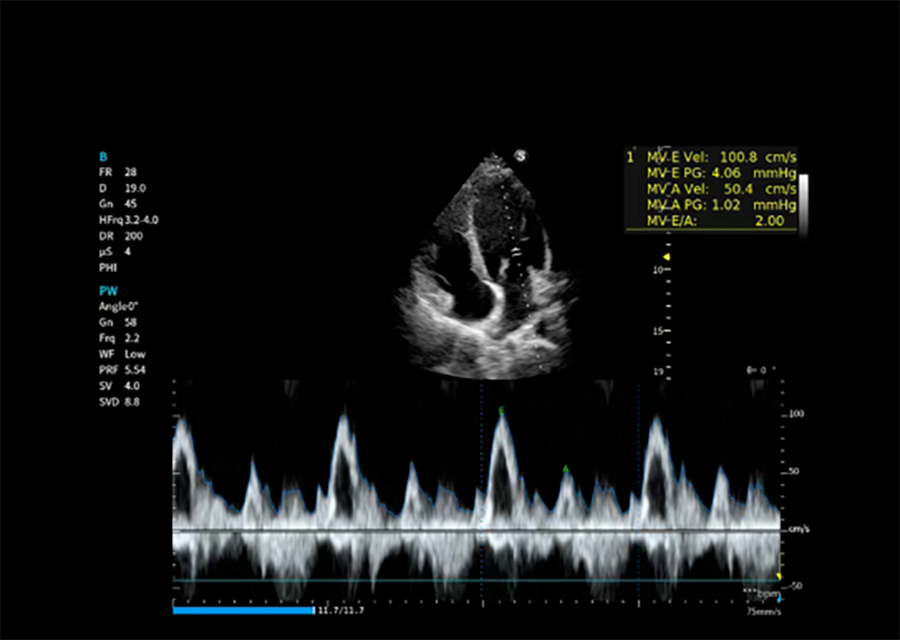

心脏自动测量

简化心血管检查操作步骤,缩短检查时间,协助医生快速完成心脏参数测算与诊断。